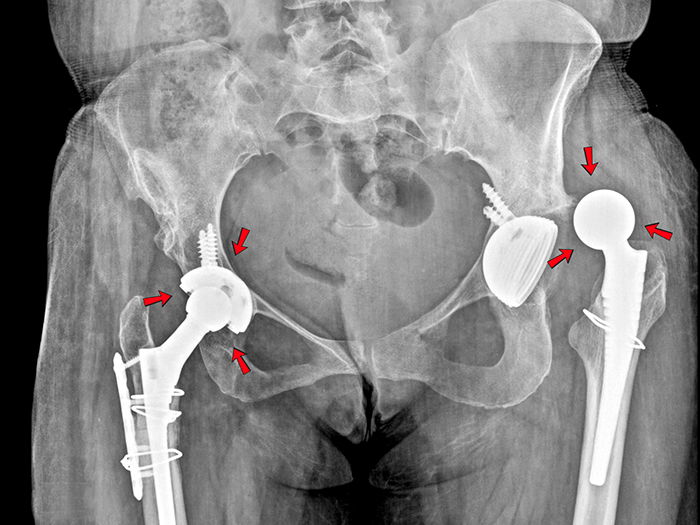

Gây mất cân bằng khớp gối và khớp háng

Chân cong làm trục xương không thẳng, khiến trọng lượng cơ thể dồn lệch sang một bên chân. Lâu dài, điều này gây mài mòn khớp gối, lệch khớp háng và có thể dẫn đến thoái hóa khớp sớm khi trưởng thành.

Lệch khớp háng là tình trạng biến chứng nguy hiểm dễ dẫn tới dị tật chân, khiến việc đi lại bất thường